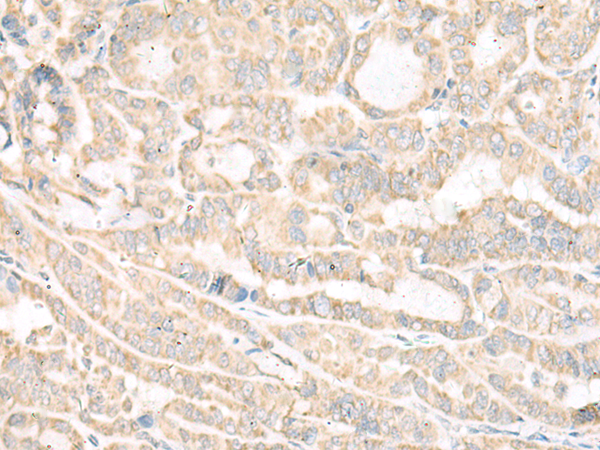

ELISA, IHC |

IHC positive control: |

Human thyroid cancer and Human cervical cancer |

IHC Recommend dilution: |

30-150 |